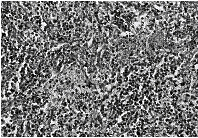

病變部位淋巴結腫大,正常結構破壞,部分或全部被腫瘤組織所代替。鏡下可見淋巴結被浸潤如肉芽腫,其中可

霍奇金病發現不同的病理變化與預後關係很大,為了採取不同的有效治療,有必要進一步分型。國際多採用Rye分型,依預後良差分為四型。

1.淋巴細胞優勢型是分化最好的類型,亦可被認為是霍奇金病的早期階段,其惡性程度比較低,病灶常局限於一個或一組淋巴結。臨床症狀很輕或沒有任何不適。鏡下在正常淋巴組織結構消失的區域內,淋巴細胞和組織細胞呈不同比例的增生,而常以小淋巴細胞增生為主;司-瑞細胞少見且不典型。淋巴結無壞死性改變。這種淋巴結與炎症性病變最難區別,容易漏診。此型約占本病的10%~20%,預後最佳。

2.結節硬化型此型很少演變成其他類型。好發於縱隔淋巴結,也可同時累及鎖骨上淋巴結,極少見於腹腔淋巴結,臨床發展緩慢。病變中有較多的膠原纖維束將腫瘤細胞分割成一個個結節。司-瑞氏細胞常見於裂隙狀的空白內,亦稱裂隙細胞(lacunarcell),是小兒時期最常見的類型,約占本病的半數,預後僅次於淋巴細胞優勢型。

3.混合型可由淋巴細胞優勢型演變而來。臨床多數有明顯的症狀。淋巴結的結構瀰漫性消失,但在淋巴結最初受累時只有部分結構破壞,病變中有各種不同的細胞包括淋巴細胞、組織細胞、嗜酸性粒細胞和漿細胞,並有典型的雙核、分葉核或多核的有較大核仁的司-瑞細胞。這種類型變化多樣,典型的很易診斷,不典型的與炎性肉芽腫、結核、反應性增生易相混淆。此型約占本病的10%以上。診斷時多有淋巴結外浸潤,預後較差。

4.淋巴細胞削減型可由淋巴細胞優勢型直接演變,或由混合型轉變而來,為淋巴瘤的晚期,是分化最差的類型,病情發展迅速。病變中淋巴細胞很少,又可分為兩種形式,一種由透明膠原纖維構成的瀰漫性硬化,淋巴細胞顯著稀少,淋巴結體積可以縮小;一種主要由大量異型網狀細胞組成,司-瑞氏細胞容易找到。此型約占10%,預後最差。